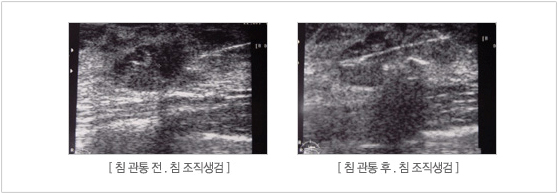

»ó±â ȯÀÚ´Â ¿ÞÂÊ °¡½¿¿¡ ¸ù¿ì¸®(BREAST MASS)°¡ ¸¸Á® Áø´Ù°í ³»¿øÇÏ¿© ÃÊÀ½ÆÄ °ËÁø°ú (ÃÊÀ½ÆÄ »çÁø)

Á¶Á÷ °Ë»ç ¸¦ ½ÃÇà ÇÏ¿© °Ë»ç °á°ú »ó±â Áø´Ü¸í(Á¡¾×¼º À¯¹æ¾Ï)À¸·Î Áø´Ü µÇ¾î (Á¶Á÷°Ë»ç°á°úÁö)